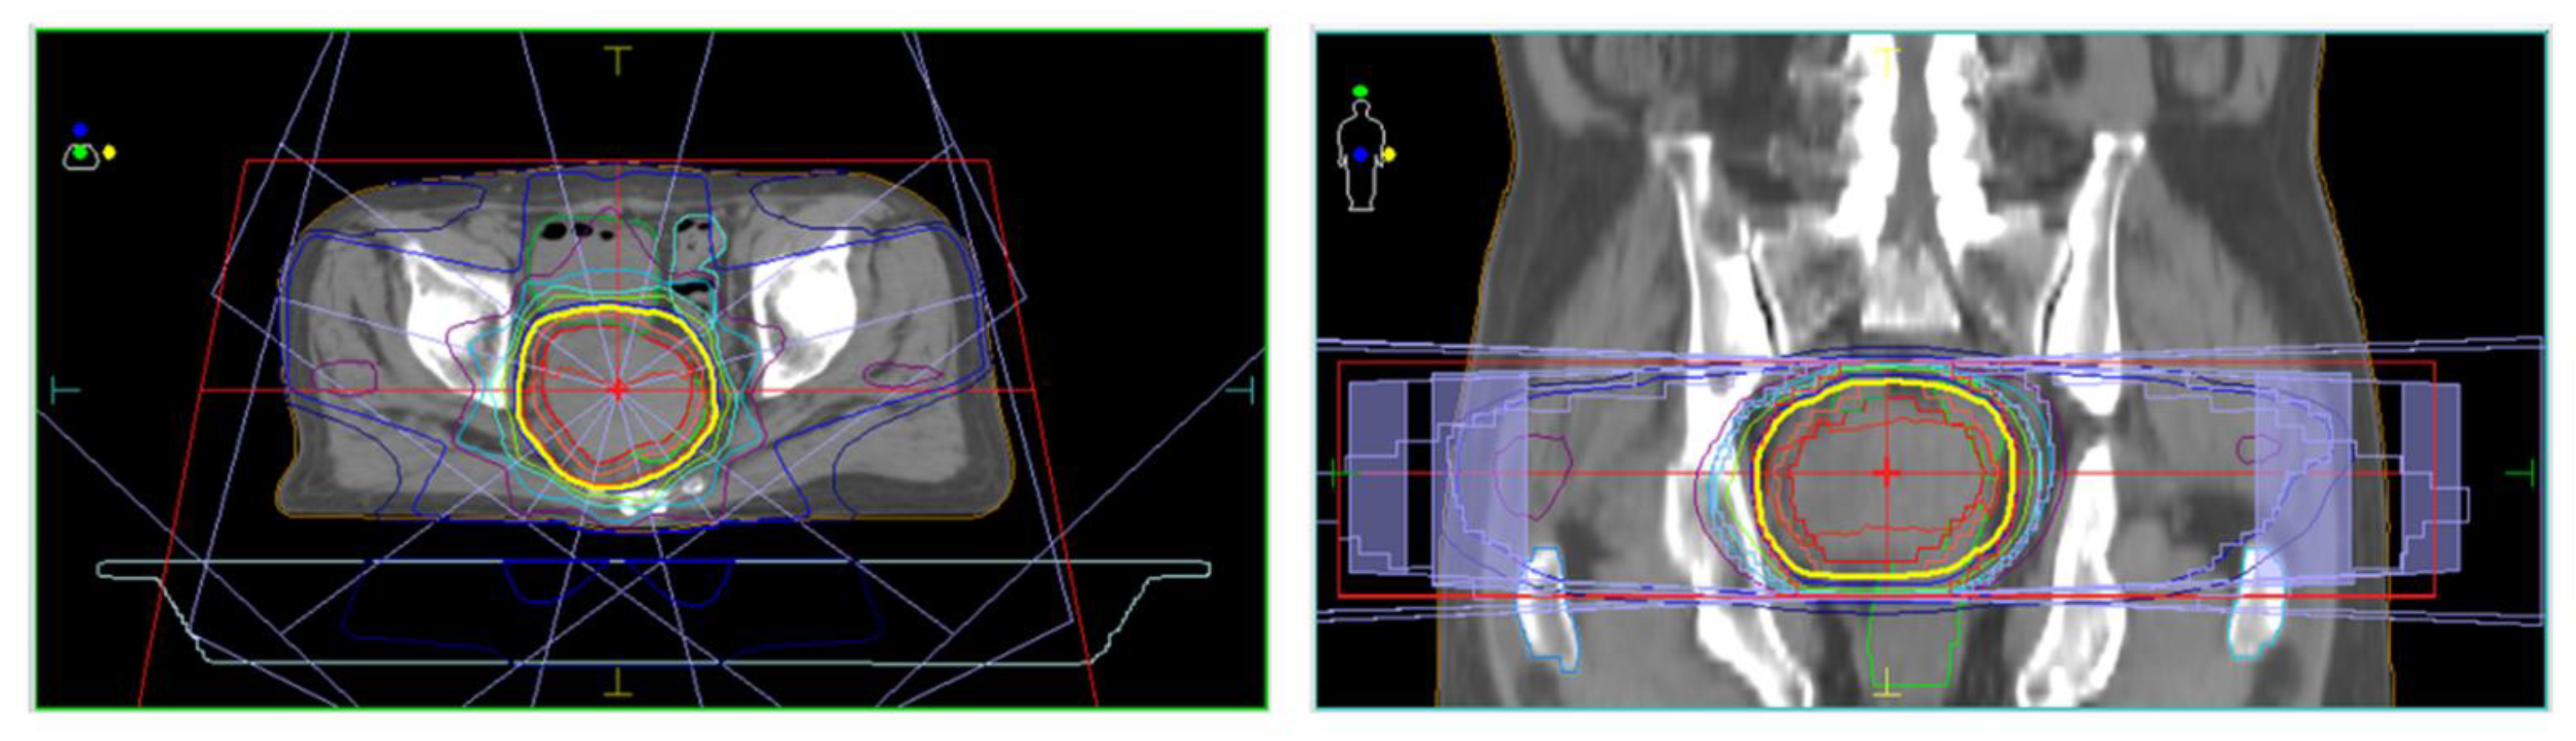

| August–October | 3D-CRT (prescribed dose for the gross tumor: 60 Gy in 30 fractions) | |

| (Decrease in the tumor size and DCP values, constipation resolved) | ||